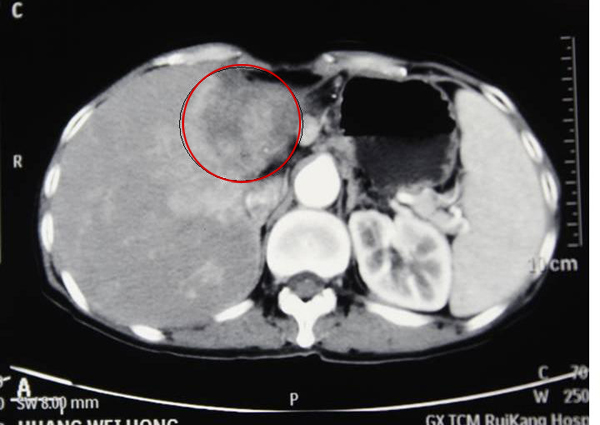

黄女士治疗前肝肿瘤(红圈内)

贵港黄女士是2013年确诊为胆管细胞癌,当时癌肿已有6-7厘米大。经过十天左右的射波刀治疗,同时运用中草药扶正抑制癌肿治疗。持续服用中药9个月后,她再次来到了瑞康医院进行磁共振检查,让黄女士感到惊喜的是:肝脏巨大肿块竟然明显缩小了,而且其他部位没见新病灶。如此良好的效果是中西医结合“三联疗法”的作用。